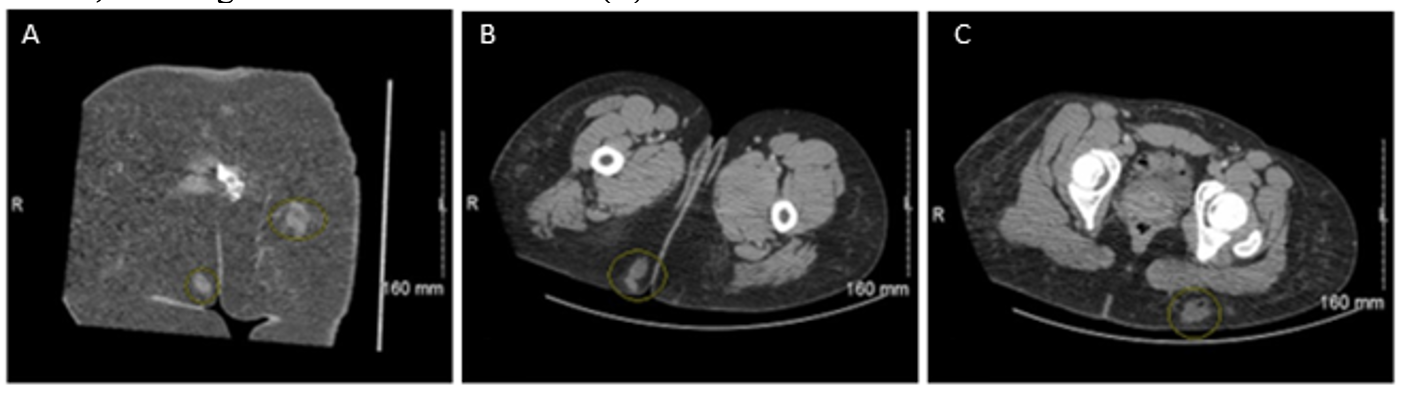

On presentation to our institution 3 months after her initial surgery, the patient had complaints of immense pain and tenderness of the left buttock with firm underlying induration without any open wounds. She was started on vancomycin and metronidazole (Figure 4). Ultrasound of the breast and buttocks did not show fluid collection. Chest X-ray and computed tomography (CT) of the chest, abdomen, and pelvis did not reveal any acute disease. NTM infections were of concern given her recent overseas surgery. After 4 days of broad-spectrum antibiotics, the underlying induration coalesced into a drainable fluid collection. Aspiration of this revealed purulent fluid that grew Mycobacterium fortuitum. Moxifloxacin and imipenem were begun, and she ultimately required formal I&D that revealed significant underlying fat necrosis (Figure 5). The wound was treated with negative pressure wound therapy with multiple subsequent I&Ds. Three months later, she returned to the emergency department with left buttock pain, and a CT scan showed new fluid collections (Figure 6). Doxycycline and trimethoprim-sulfamethoxazole (TMP-SMX) were started based on Mycobacterium fortuitum susceptibility studies. She underwent 2 additional I&D procedures of the bilateral buttocks until the wounds were closed a week later. She was ultimately discharged on doxycycline and TMP-SMX and has not had any further recurrence (Figure 7).